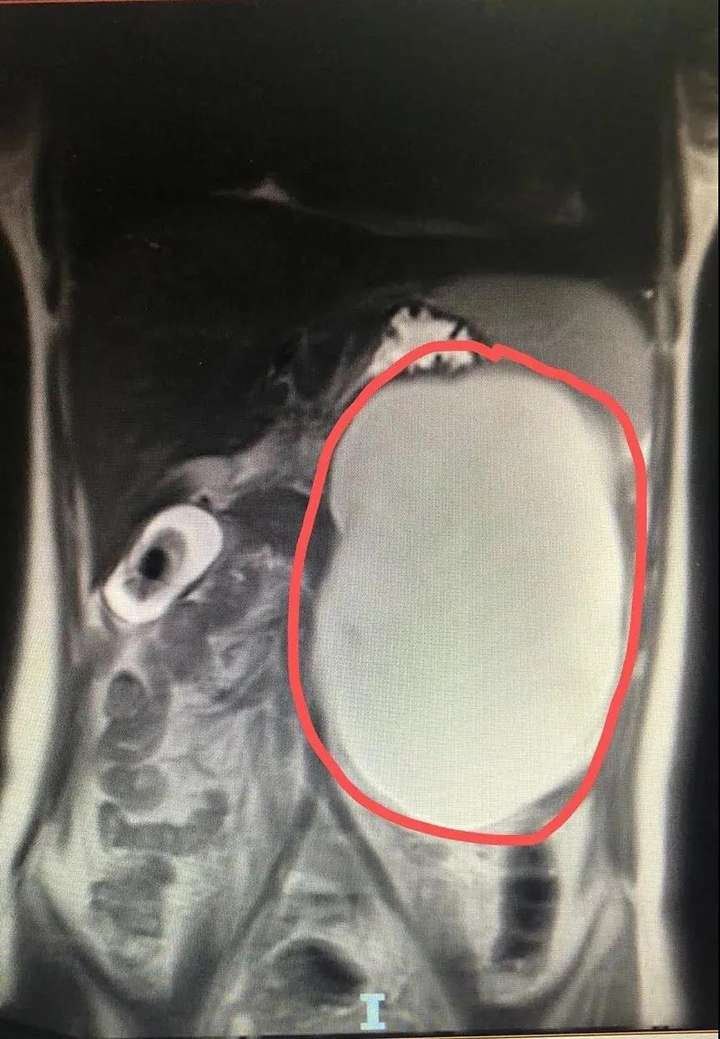

胃胰之间有一个巨大囊性包块,里面积满了液体,跟个“大水球”似的占据了左腹腔,还把这里的“原住民”——胃和小肠等内脏硬生生地挤到了右边。

▲患者腹部CT图,红圈区域为囊肿,占据整个左腹腔

不过好在,这个“庞然大物”看着吓人,但应该为良性病变,这让小微悬着的心稍稍放了下来。